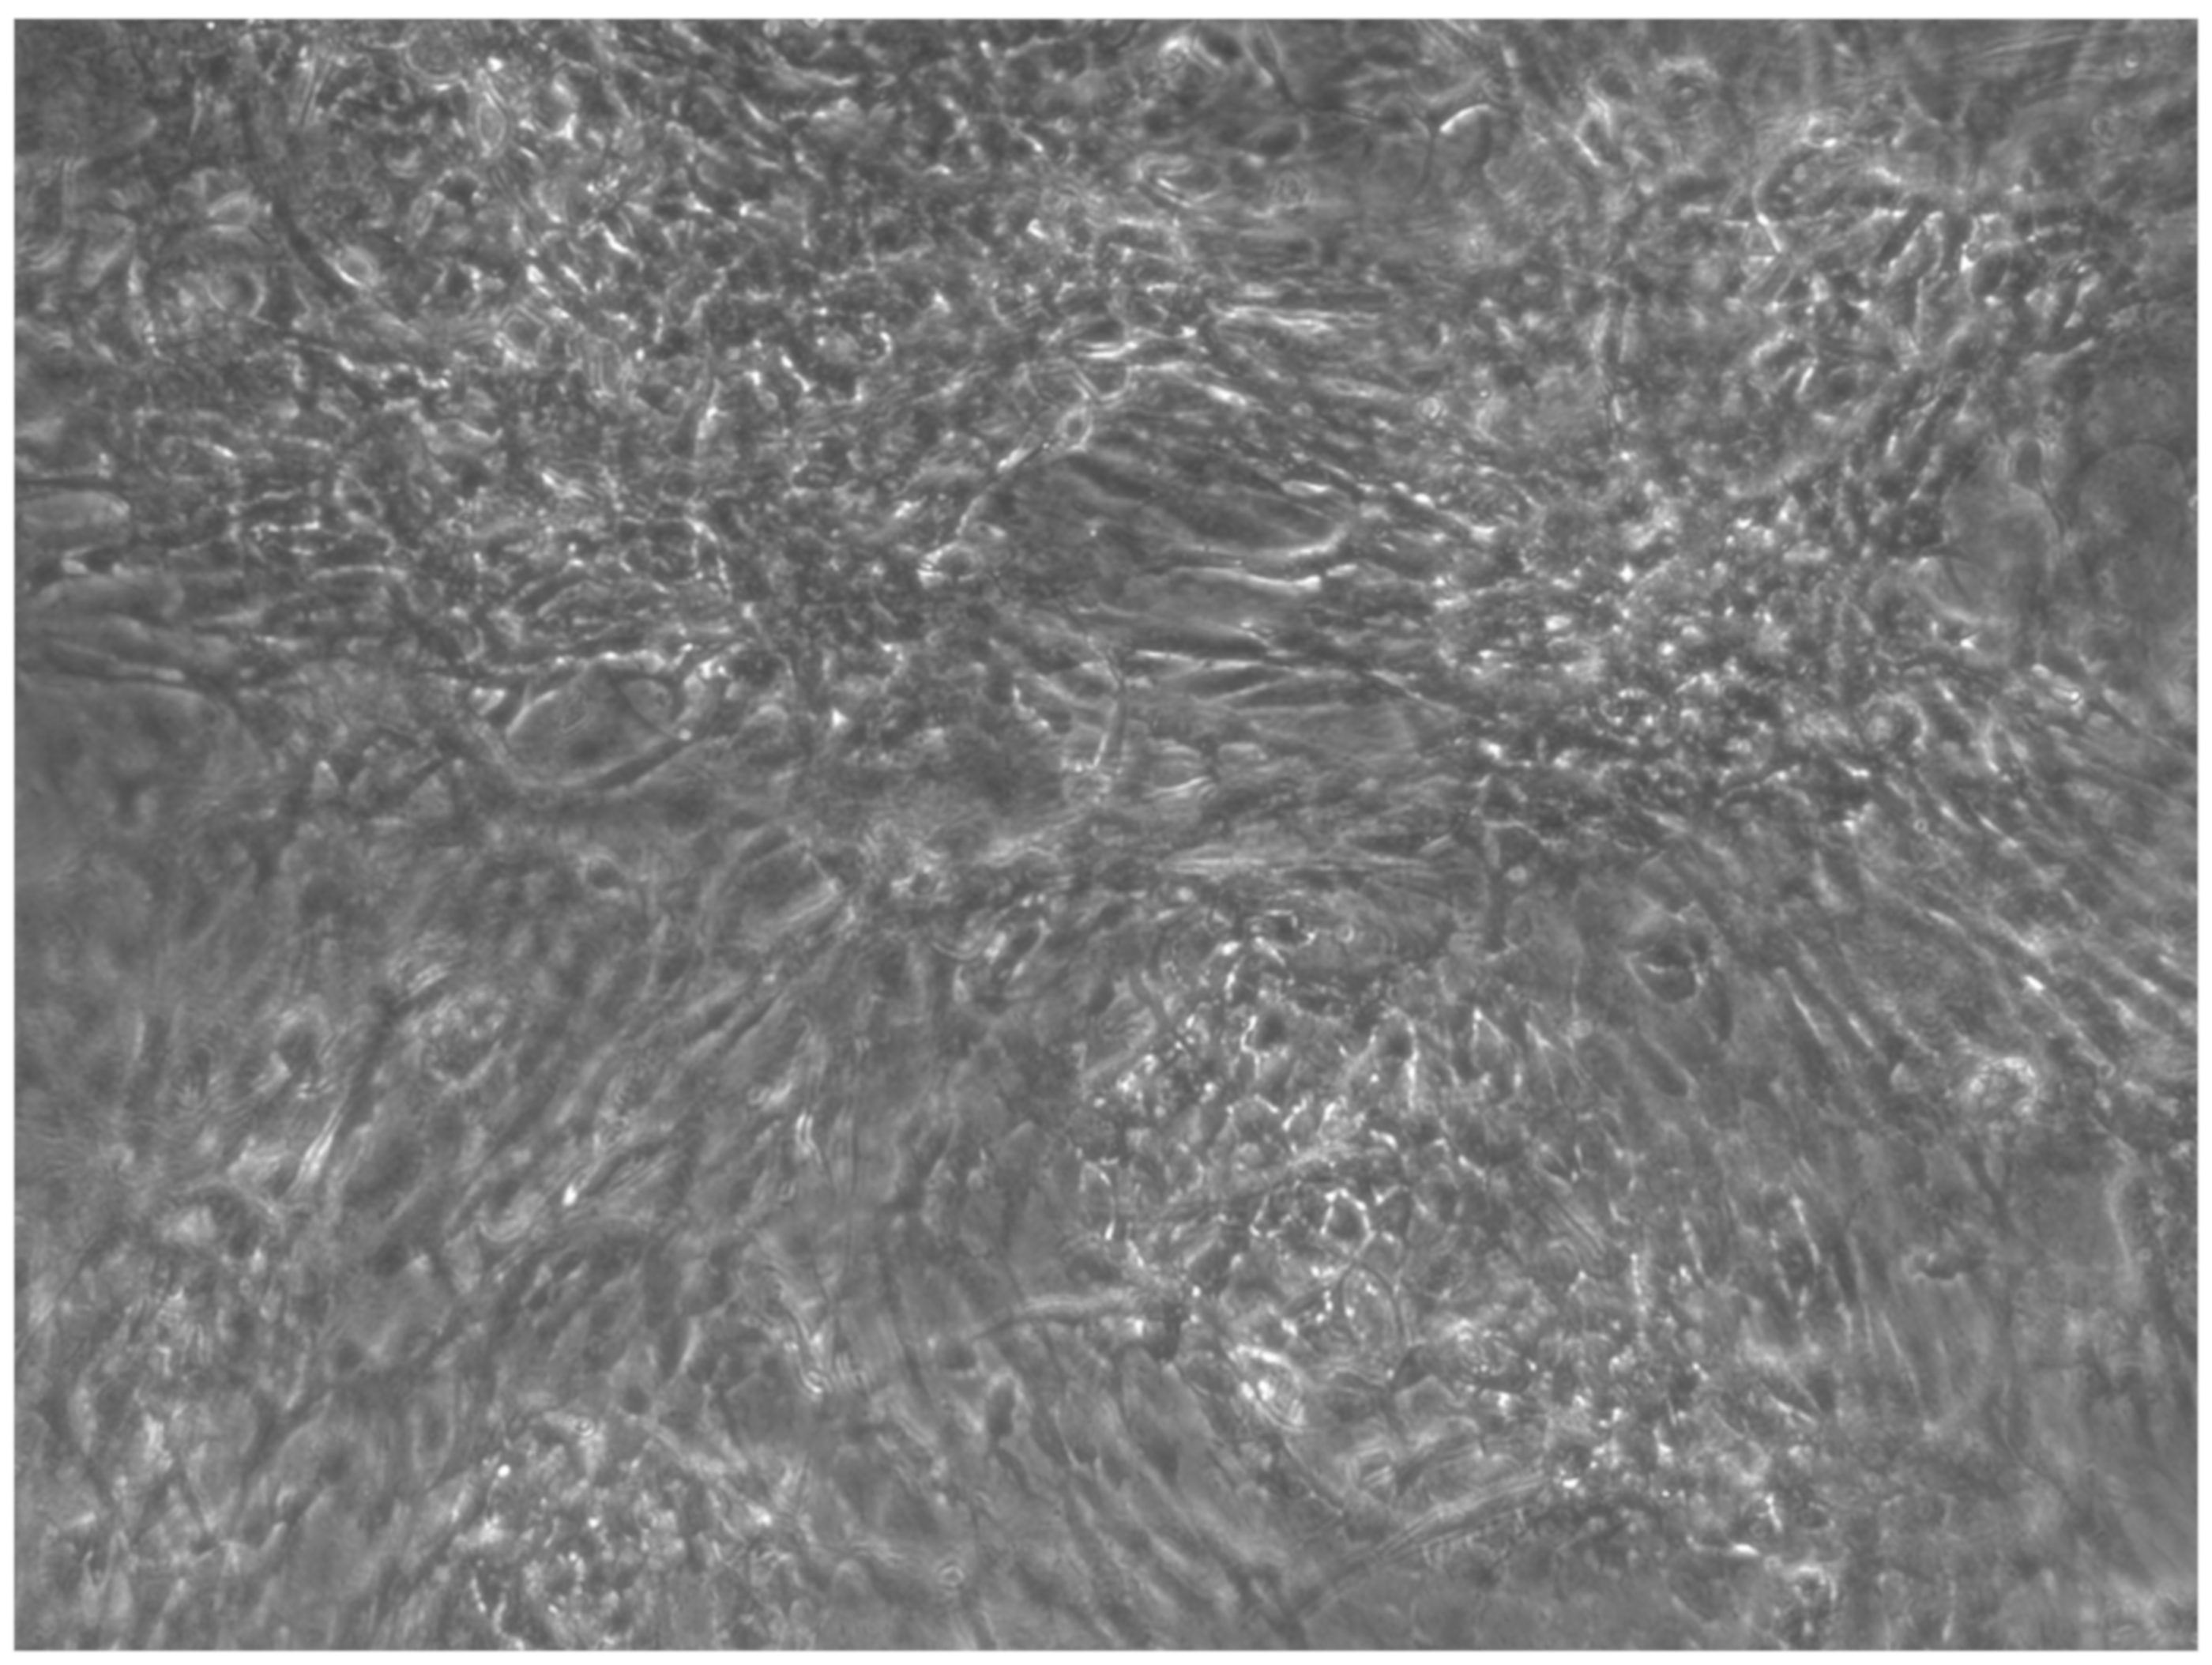

Figure 5.

CTR8#14 P12 – RA showed the typical image of bone formation, where the collagen fibers, which make part of the extracellular matrix, begin to be arranged in a concentric way, thus giving a rudimentary appearance to the osteon, but one which is typical of the early stages of osteogenesis.

Figure 6.

Since the first images processed under the microscope after staining with alizarin, we see that those after 14 days are positive to the test of alizarin, so the partially differentiated cells include calcium. We have one image for control CTR2#6 P19 (a), five images for CTR8#14 P12 – RA (b–f) control, being the best clone, and one image for control CTR8#14 P12 + retinoic acid (g).